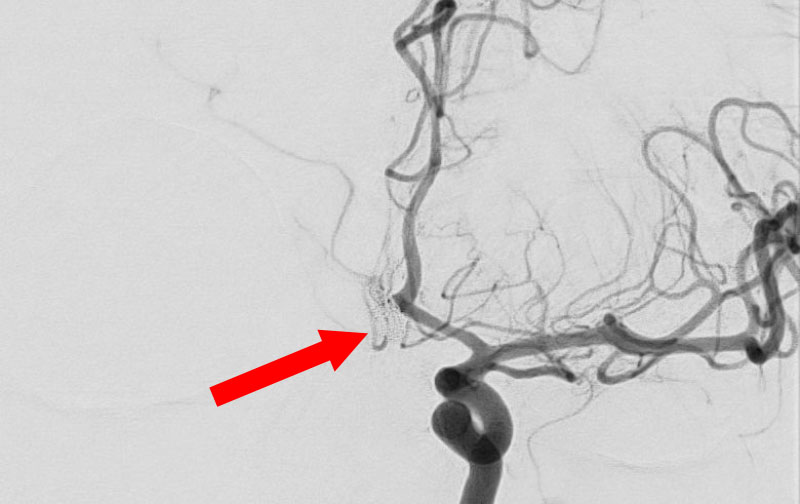

No.1593 手術後